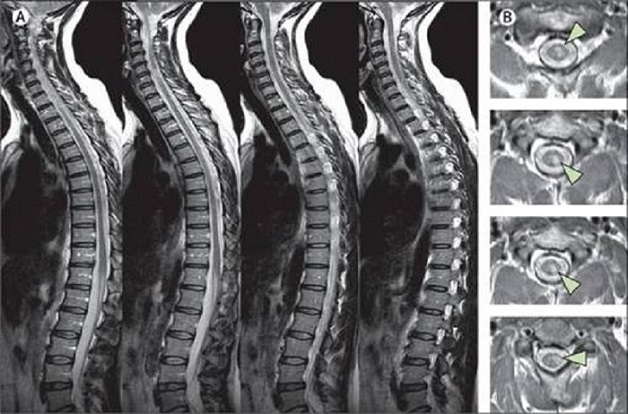

Thông qua những hình ảnh thu được sẽ cho phép thấy rõ về hình thái, cấu trúc cho tới các tổn thương ở phần mềm, dây chằng, đĩa đệm hoặc mô mềm một cách rõ ràng. Cũng chính vì vậy mà việc chẩn đoán, đánh giá các bệnh lý ở cột sống thắt lưng sẽ trở nên dễ dàng và chính xác hơn nhiều.

Bên cạnh đó, cộng hưởng từ còn giúp bác sĩ chẩn đoán tốt các tổn thương ở thân đốt sống, đĩa đệm, tủy sống và tổ chức phần mềm ở quanh cột sống nhờ hình ảnh cột sống thu được từ phương pháp chụp MRI rõ nét và chi tiết.

Chụp MRI giúp phát hiện nhiều bệnh lý vùng cột sống thắt lưng